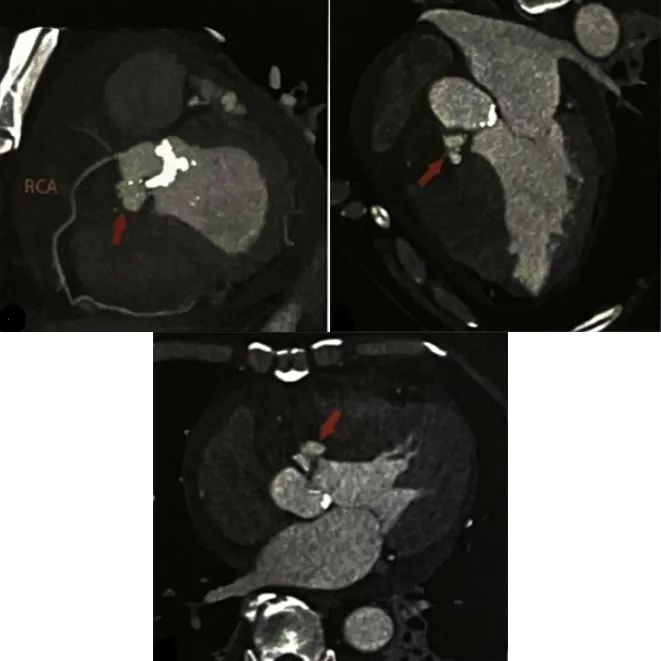

冠状动脉CTA (图2)显示右冠状动脉起源走行正常,未见狭窄;左冠状动脉正常,未见狭窄。主动脉瓣增厚、钙化,主动脉瓣环右前下方可见一个局限性造影剂池凸起。

图2 冠状动脉CTA